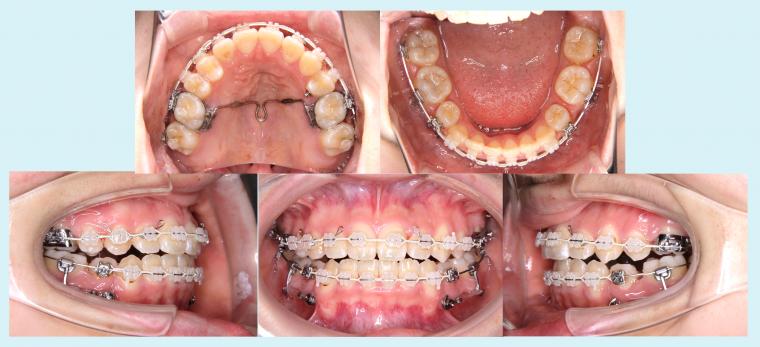

#44 上顎歯列の狭窄を伴う叢生症例